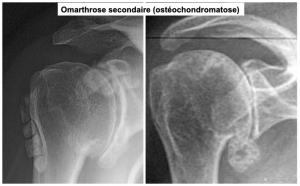

L'Arthrose et la Polyarthrite Rhumatoïde entraînent des déformations des articulations, craquements, dérobements, sensation d'accrochage et pseudo blocages et elles peuvent se développer.

Les articulations sont sollicitées et le cartilage s'use progressivement. Le cartilage disparaît pour laisser l'os à nu. Elles peuvent toucher la colonne vertébrale et les articulations les plus atteintes sont celles : des mains, des poignets, des hanches, des genoux et des pieds.